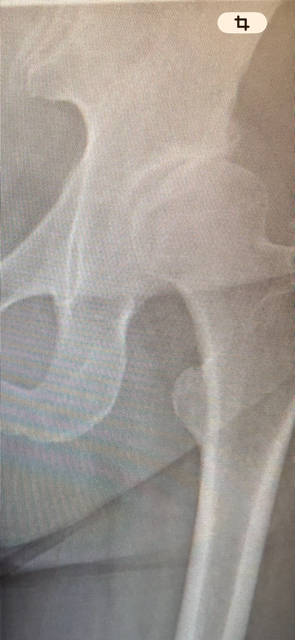

股関節痛・変形性股関節症専門コース

股関節:変形性股関節症

【喜びの声】変形性股関節症 激痛で歩くことが出来きない。 現在、痛みなく歩行出来る様になる。

①どのような症状で来院されましたか? 左の変形性股関節症。整形外科では(年…

変形性股関節症 激痛で歩くことが出来きない。 現在、痛みなく歩行出来る様になる。